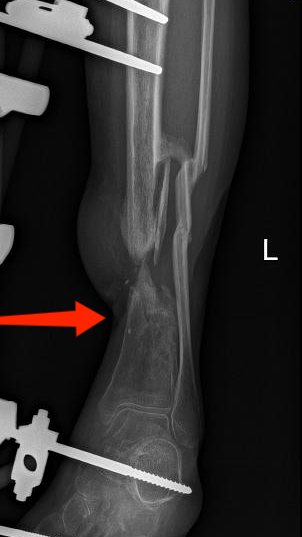

多年来,贵州航天医院各科室紧跟医学前沿,不断强技术、补短板,大力开展新技术、新项目,完成了许多高精尖、高难度、本地区“首例”的技术,填补了医院医疗技术空白,满足了群众日益增长的医疗需求。 贵州航天医院骨科率先在遵义地区开展骨搬移技术,截至目前,已治愈慢性骨髓炎、感染性骨不连、骨缺损、脉管炎、糖尿病足患者200余例,糖尿病足治疗保肢率达到98%。 本期,我们将为大家带来骨科特色技术——骨搬移技术(Ilizarov)。 案例分享 一名59岁的患者,身患糖尿病12年,在来我院3个月前出现了右脚溃烂的症状,来院就诊时,患者的右脚十分红肿,右脚脚趾坏死,伤口处不断流出黑红色脓液,情况十分严重。在接诊到患者时,骨科专家团队高度重视,立刻为患者完善了CT血管造影(CTA)等相关检查,诊断为:2型糖尿病,糖尿病周围血管病变,右糖尿病足。 术 前 考虑到患者情况比较严重,为最大限度保证患者肢体完整,科室专家团队进行了严格的讨论评估,为患者制定了骨搬移技术治疗方案,在征得患者及其家属的同意后,成功通过搬移骨块为患者进行治疗,促进患者病变肢体血管再生。 胫骨横向骨搬移外架固定 清除感染病灶 术后调节外架,通过搬移骨块 促进患肢血管再生 患者在术后三周前来换药,观察到感染得到进一步控制;术后六周复查,患者病变处已愈合,进行CT血管造影(CTA)后可明显观察到足部血管再生。 术后3周 术后6周愈合 CT血管造影见足部血管再生 糖尿病患者全身与局部的问题互为影响,形成恶性循环,糖尿病足溃疡创面迁延不愈,常见干性坏疽、湿性坏疽、趾坏死、深且大的溃疡以及骨髓炎等症状,还可导致脓毒血症,以往为保全生命,患者被迫选择一次或多次截肢。骨搬移技术的发展进步,能在血糖有效控制、局部有效清创下,有效促进患肢微血管再生,改善患肢血供,达到糖尿病足更快治疗康复的目的,并能根据病变情况最大限度的保障患者肢体完整。 什么是骨搬移技术 骨搬移技术是通过使用专用的骨外固定器固定骨段,每天缓慢牵拉,在牵拉搬移过程中,骨段尾部形成新骨及新的软组织,从而修复骨骼缺损及软组织缺损。是治疗大段骨缺损、骨不连、骨感染、肢体畸形的金标准方法,也用于治疗脉管炎、糖尿病足等肢体缺血性疾病。 骨感染缺损 切除感染段 搬移骨段 新骨形成 骨感染根治愈合 骨搬移技术原理 生物组织在持续、稳定、缓慢牵拉下,能刺激细胞分裂、组织再生,骨外固定技术运用该原理,通过持续缓慢调节外固定器形成牵拉张力,促进牵引成骨与相邻组织再生,如神经、血管、肌肉、皮肤等再生,达到治疗大段骨缺损、肢体缺血如糖尿病足等疾病的目的。 骨搬移技术优势 (一)除治疗骨缺损、骨不连外,有更广的适用范围,利用组织再生、血管再生等特性,能大量运用于肢体畸形的矫形、糖尿病足等的治疗。 (二)治疗效果确切,重建肢体外型和功能,极大降低截肢率和残疾率。 (三)明显提高了患者生活质量,极大减轻其家庭及社会负担。 肢体畸形的矫形 慢性骨髓炎 骨段切除 术后1年 濒临截肢的脉管炎术后6周 难愈创面术后3周 贵州航天医院骨科 专家团队 赵学平 骨科主任 主任医师 临床擅长:从事骨科临床工作30余年,对骨科常见疾病的诊治具有丰富的临床经验。 世界中医药联合会脊柱康复专业委员会常务理事,中华中医药学会整脊分会常务委员,中国中西医结合学会骨伤科分会肢体矫形功能重建与康复专家委员会常务委员,中国研究性医院学会骨科创新与转换专业委员会关节外科学组保髋工作委员会常委,中国康复技术转化及发展促进会骨外科与康复技术转化专业委员会常务委员,泛珠三角区域运动医学联盟(PPRD-SMA)理事会常务理事,中国研究型医院学会运动医学专业委员会委员,贵州省中医药学会整脊分会副主任委员,贵州省中西医结合学会银质针专业委员会副主任委员,贵州省康复医学会骨与关节专业委员会常务委员,贵州省人民医院骨科专科联盟常务理事,贵州省康复医学会骨内科专业委员会常务委员,中华医学会贵州省骨科学会委员,贵州省康复医学会脊柱脊髓专业委员会常务委员,贵州省运动医学分会委员,贵州省康复医学会骨与软组织肿瘤专业委员会委员,遵义市医学会创伤分会副主任委员,贵州省康复医学会骨内科专业委员会遵义地区分会常务委员,遵义市医疗事故鉴定、伤残鉴定、工伤鉴定、司法鉴定专家。 长期从事骨科临床研究及教学工作,在国家级、省部级杂志发表论文20余篇,SCI论文2篇,参与主编骨科专著2部,主持省部级科研项目2项,参与指导省部级、市级科研项目6项。 陈明勇 骨科副主任 副主任医师 临床擅长:从事创伤骨科工作约20年,对骨缺损、骨不连、骨肿瘤、肢体畸形等的肢体矫形重建及功能重建,慢性化脓性骨髓炎的根治治疗、糖尿病足的保肢治疗、快速康复理念(ERAS)下的老年骨折的诊治,四肢复杂骨折的诊治,四肢骨折等微创手术治疗具有丰富的临床经验。 2004年毕业于遵义医学院临床专业,曾在中国人民解放军总医院、广西医科大学第一附属医院、上海第六人民医院骨科进修。中国中西医结合学会骨伤科专业委员会横向骨搬移治疗糖尿病足及微血管网再生学组首届委员,遵义市医学会创伤分会常务委员。 瞿 辉 骨科 副主任医师 临床擅长:对骨科的常见病、关节外科、脊柱外科及运动医学疾病的诊治具有丰富的临床经验,熟练掌握骨科手术操作技术。 毕业于遵义医学院临床医学系,2005年前往广州中山大学第一附院骨显微医学部进修学习,2011年前往成都华西医院进修学习,并多次在省内外学习骨科相关知识,是中华医学会骨科分会会员。 赵兴东 骨科 主任医师 临床擅长:擅长骨科的常见病及各种创伤、四肢骨折创伤修复、骨感染、手足疾病的诊治和手足体表畸形的矫形整复,熟练掌握骨科四肢骨病及创伤的手术操作技术,尤其在四肢关节复杂性损伤、手足外伤、组织缺损创面、难治创面的皮瓣修复方面及平足、高弓足矫形方面及四肢慢性疼痛诊治、康复方面具有丰富的临床经验。 硕士研究生,毕业于遵义医学院临床外科系,2015年前往山东省立医院手足外科进修学习;遵义市医学分会创伤分会第一、二届委员,遵义市手外科医学会第二委届员会常务委员;在省级及省级以上期刊发表文章9篇,参编著作2部,参与主持并完成市级课题1项,参与市级课题2项、省级课题1项。 张俊凯 骨科 副主任医师 临床擅长:从事骨科临床工作28年,对创伤骨折、骨感染、骨缺损、骨不连等外科诊治,四肢骨折的微创手术治疗,四肢复杂骨折(如关节内粉碎性骨折、多发骨折等)的损伤控制及手术治疗等具有丰富的临床经验。 1995年毕业于遵义医学院临床专业,2009年前往复旦大学附属医院骨科进修1年。 卢懿明 骨科 副主任医师 临床擅长:从事骨科工作18年,对创伤骨折、四肢骨折的微创手术治疗、四肢复杂骨折(如关节内粉碎性骨折、多发骨折等)的损伤控制及手术治疗,尤其是髋部骨折的PFNA等微创技术,踝关节骨折、膝关节周围骨折的Mipo微创技术等具有丰富的临床经验,开展了4项新技术,发明6项新型专利技术。 2005年毕业于遵义医学院临床专业,2017年,前往南方医科大学第三附属医院骨科进修半年,回院后运用Mipo技术对骨干骨折及干骺端骨折的治疗技术,同时积极开展骨盆骨折、髋臼骨折腹直肌外侧切口的应用;发表了多篇专业论文,经常参与省内外学术交流会授课,获得医院荣誉称号多个。 邬夏荣 骨科 副主任医师 临床擅长:从事骨科工作16年,对四肢复杂骨折、骨肿瘤的诊治,尤其是足踝创伤、慢性踝关节损伤、平足症等诊疗具有丰富的临床经验。 2006年毕业于遵义医科大学临床医学专业,曾在陆军军医大学西南医院进修学习,发表多篇骨科学术论文。 余德怀 骨科 副主任医师 临床擅长:从事骨科工作10余年,对运动医学、骨关节、脊柱外科常见病、多发病的诊治具有丰富的临床经验。 硕士研究生,2011年毕业于遵义医学院临床医学专业,曾前往遵义医科大学附属医院运动医学专业进修学习;是贵州省医学会运动医学分会青年委员,西部关节镜联盟委员;发表多篇骨科学术论文。 冯 乾 骨科 副主任医师 临床擅长:从事骨科工作近20年,熟练掌握骨科多发病及常见病的诊治,尤其对脊柱退变性疾病的诊断及治疗具有丰富的临床经验,主要研究脊柱微创相关治疗方式,能熟练开展椎间孔镜及VBE。 曾前往北京大学第三医院进修学习疼痛及椎间孔镜、首都医科大学友谊医院专业进修脊柱内镜;是贵州省康复医学会第三届脊柱脊髓专业委员会委员;发明专利3项、发表脊柱外科专业论文多篇。 张艳金 骨科 副主任医师 临床擅长:从事骨外科工作16年,对复合伤、多发伤的救治、四肢骨干骨折、关节周围骨折、骨肿瘤、骨髓炎等诊治具有丰富的临床经验。 中共党员,硕士研究生,2006年本科毕业于山西医科大学第二临床医学院,2011年研究生毕业于北京军区总医院;在“老年COPD患者合并髋部骨折的诊治”国际合作课题组研究两年,在老年髋部骨折的诊治方面具有丰富的经验,并发表论文6篇;承担遵义市级课题1项;承担遵义医科大学的临床教学工作,获得遵义医科大学优秀带教老师荣誉。编撰有《骨科疾病诊疗精粹》一书,开展2项新技术,编撰地方规范《务川自治县创伤骨科常见疾病诊疗规范》一书。 赵小锋 骨科 副主任医师 临床擅长:从事骨科临床工作11年,对骨科常见病、多发病诊疗有较为丰富的临床经验,擅长脊柱相关疾病诊断及治疗,尤其是颈、腰、腿疼痛疾病诊断及治疗,擅长胸腰椎骨折微创经皮穿刺内固定术、经皮穿刺椎体成形术、经皮穿刺脊柱内镜下腰椎间盘摘除术、单纯开创腰椎间盘摘除术、腰椎滑脱复位椎间植骨椎融合内固定术、腰椎管狭窄减压融合内固定术及人工髋、膝关节置换术等。 2012年毕业于遵义医学院外科学专业硕士研究生,2019年参加“遵义市115医学人才精英计划”于上海交通大学第一附属医院培训学习,2023年于北京大学第三人民医院脊柱外科进修学习,曾获得遵义市优秀医师荣誉称号。 遵义市手外科第一届委员,遵义市医学会创伤分会第一届委员,遵义市医学会创伤分会第二届委员,贵州省康复医学会第三届脊柱脊髓专业会委员,遵义市医学会烧伤与整形外科学分会委员,发表论文5篇,其中国家级核心期刊1篇,SCI论文1篇,主持市级课题1项并结题,参与市级课题2项。 贵州航天医院骨科简介 基本情况 贵州航天医院(原3417医院)骨科组建于1968年,前身是以创伤和断肢(断指)再植闻名于世的上海市第六人民医院骨科,中国断肢(断指)再植的奠基者、中科院院士陈仲伟等著名专家、学者多次莅临科室指导医疗、教,是贵州省最早拥有专业骨科技术科室之一,在70年代开展了贵州省首例断肢(断指)再植手术。组建50余年来,诊治患者已逾百万,挽救了无数的伤病员,成为了保障遵义地区人民群众健康的重要支撑。 经过几代人的不懈努力,今天的骨科,已由创伤骨科发展至骨病、骨肿瘤、骨结核等领域,现有脊柱外科、关节外科、四肢创伤、手足外科四个亚专科,成为了集医疗、教学、科研于一体的综合学科,是贵州省临床重点专科、遵义市临床重点专科、遵义市骨科临床医学中心、遵义市基层骨科专科联盟理事长单位。 科室目前开放床位110张,共有医护人员50余人,副高级以上专家18人,硕士研究生15人。拥有一流骨科医疗设备多台,每年不定期选派优秀技术骨干到全国各大知名医学院校进修、学习、参观、交流,并邀请国内、国外知名专家教授来院进行交流、指导,通过不断引进国内外先进的诊疗技术,科室医疗技术水平稳步提升,为广大人民群众提供了优质的医疗服务。 专科特色 骨一科 (一)骨缺损、骨不连的肢体与功能重建 胫骨横向骨搬移技术治疗糖尿病足: (二)慢性骨髓炎的根治治疗 (三)肢体缺血性疾病如糖尿病足、脉管炎的保肢治疗 (四)皮瓣修复 (五)复杂创伤的治疗 (六)老年髋部骨折及小儿骨折快速手术 老年髋部骨折: 骨二科 (一)胸腰椎骨折微创经皮椎弓根螺钉固定术 (二)老年性骨质疏松性患者腰椎滑脱脊柱内固定术(骨水泥螺钉) (三)V形双通道脊柱内镜技术(VBE)腰椎融合术治疗腰椎退行性疾病 (四)老年性骨质疏松性骨折(PVP/PKP)术 (五)人工髋关节置换术 (六)双侧股骨头坏死人工全髋关节置换 (七)右侧全髋置换术后假体周围骨折翻修 (八)人工膝关节置换术 (九)人工膝关节假体松动翻修 (十)关节镜技术 传统手术切口 关节镜技术切口 诊疗范围 骨一科 1.四肢创伤、矫形。 2.手、足踝外科。 骨二科